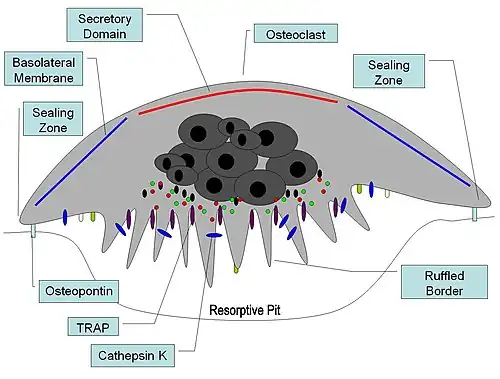

Bone remodeling

Osteopontin has been implicated as an important factor in bone remodeling.[71] Specifically, OPN anchors osteoclasts to the surface of bones where it is immobilized by its mineral-binding properties allowing subsequent usage of its RGD motif for osteoclast integrin binding for cell attachment and migration.[15] OPN at bone surfaces is located in a thin organic layer, the so-called lamina limitans.[72] The organic part of bone is about 20% of the dry weight, and counts in, other than osteopontin, collagen type I, osteocalcin, osteonectin, and alkaline phosphatase. Collagen type I counts for 90% of the protein mass. The inorganic part of bone is the mineral hydroxyapatite, Ca10(PO4)6(OH)2. Loss of bone may lead to osteoporosis, as the bone is depleted for calcium if this is not supplied in the diet.

OPN serves to initiate the process by which osteoclasts develop their ruffled borders to begin bone resorption. OPN contains and RGD integrin-binding motif